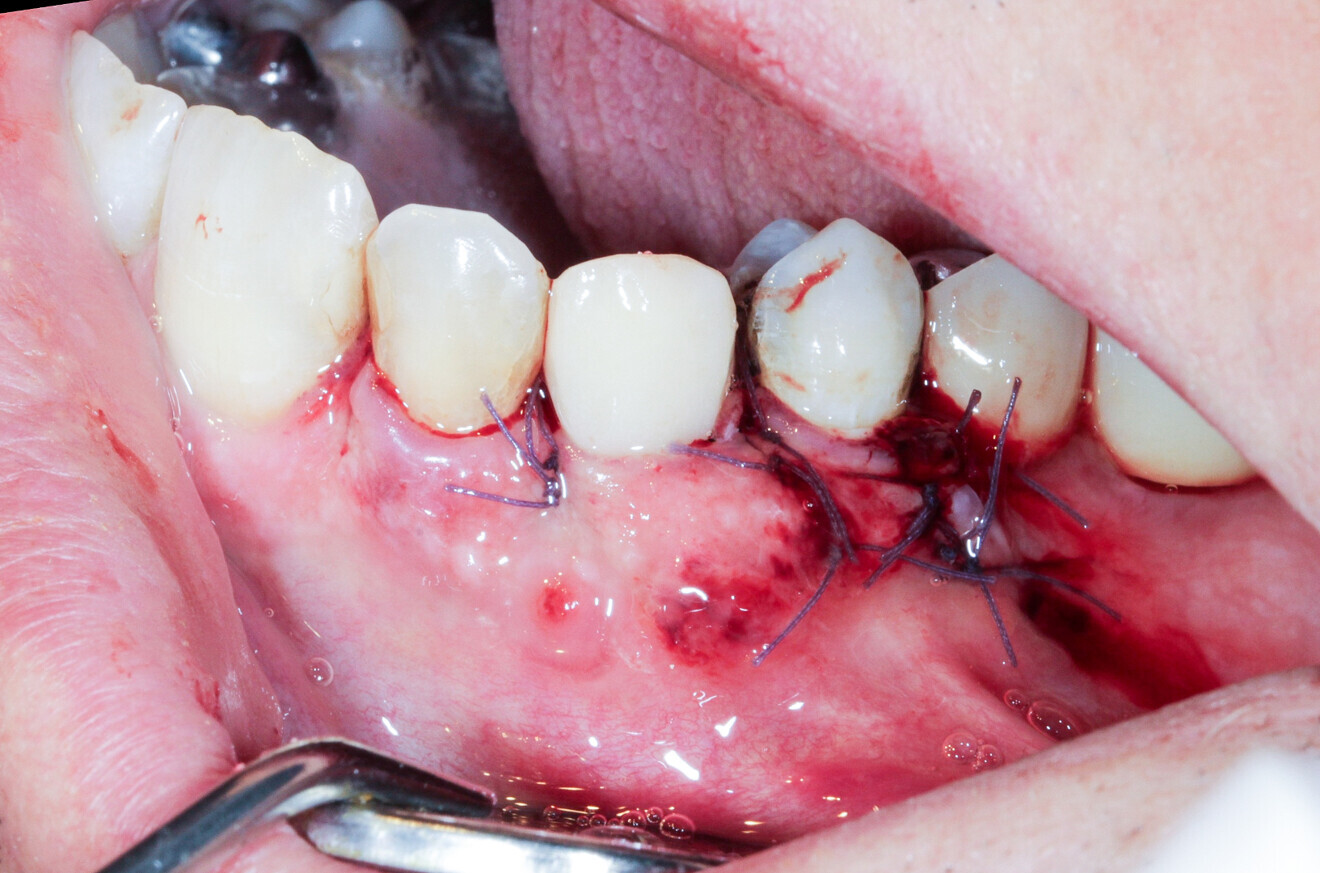

We had three alternative courses of action: a bone block graft from the mandibular ramus,2 a segmental osteotomy4 or a radicular graft, knowing that tooth #46 could not be saved. We chose the third option because it allowed for simultaneous implant placement and bone reconstruction. A large flap was elevated to assess the gap in the bone and in anticipation of closing the flap on an augmented ridge. Two implants were placed as normal despite the low residual bone thickness in the vestibular area of the planned positions for the implants (Fig. 5). The roots of tooth #46 were extracted atraumatically (root separation, use of piezo-surgery, etc.) and were then prepared as described. The roots were shaped to fit the defect and fixated at the insertion site using osteosynthesis screws (Fig. 6).3 The flap was mobilised and stretched to achieve edge-to-edge closure without tension, and a 4/0 rapidly resorbed braided thread was used for the sutures (Fig. 7). Four months after the bone augmentation and implant placement, healing abutments were connected to the implants and the osteosynthesis screws removed (Figs. 8 & 9). During the operation, time was taken to perform a visual check that ankylosis of the radicular grafts had been successful and that these were sound. Finally, a CBCT assessment was performed. The prosthesis was fitted by our colleague a few weeks later, once the soft tissue had healed.

Fig. 18: A #5/0 resorbable braided thread was used for the sutures.